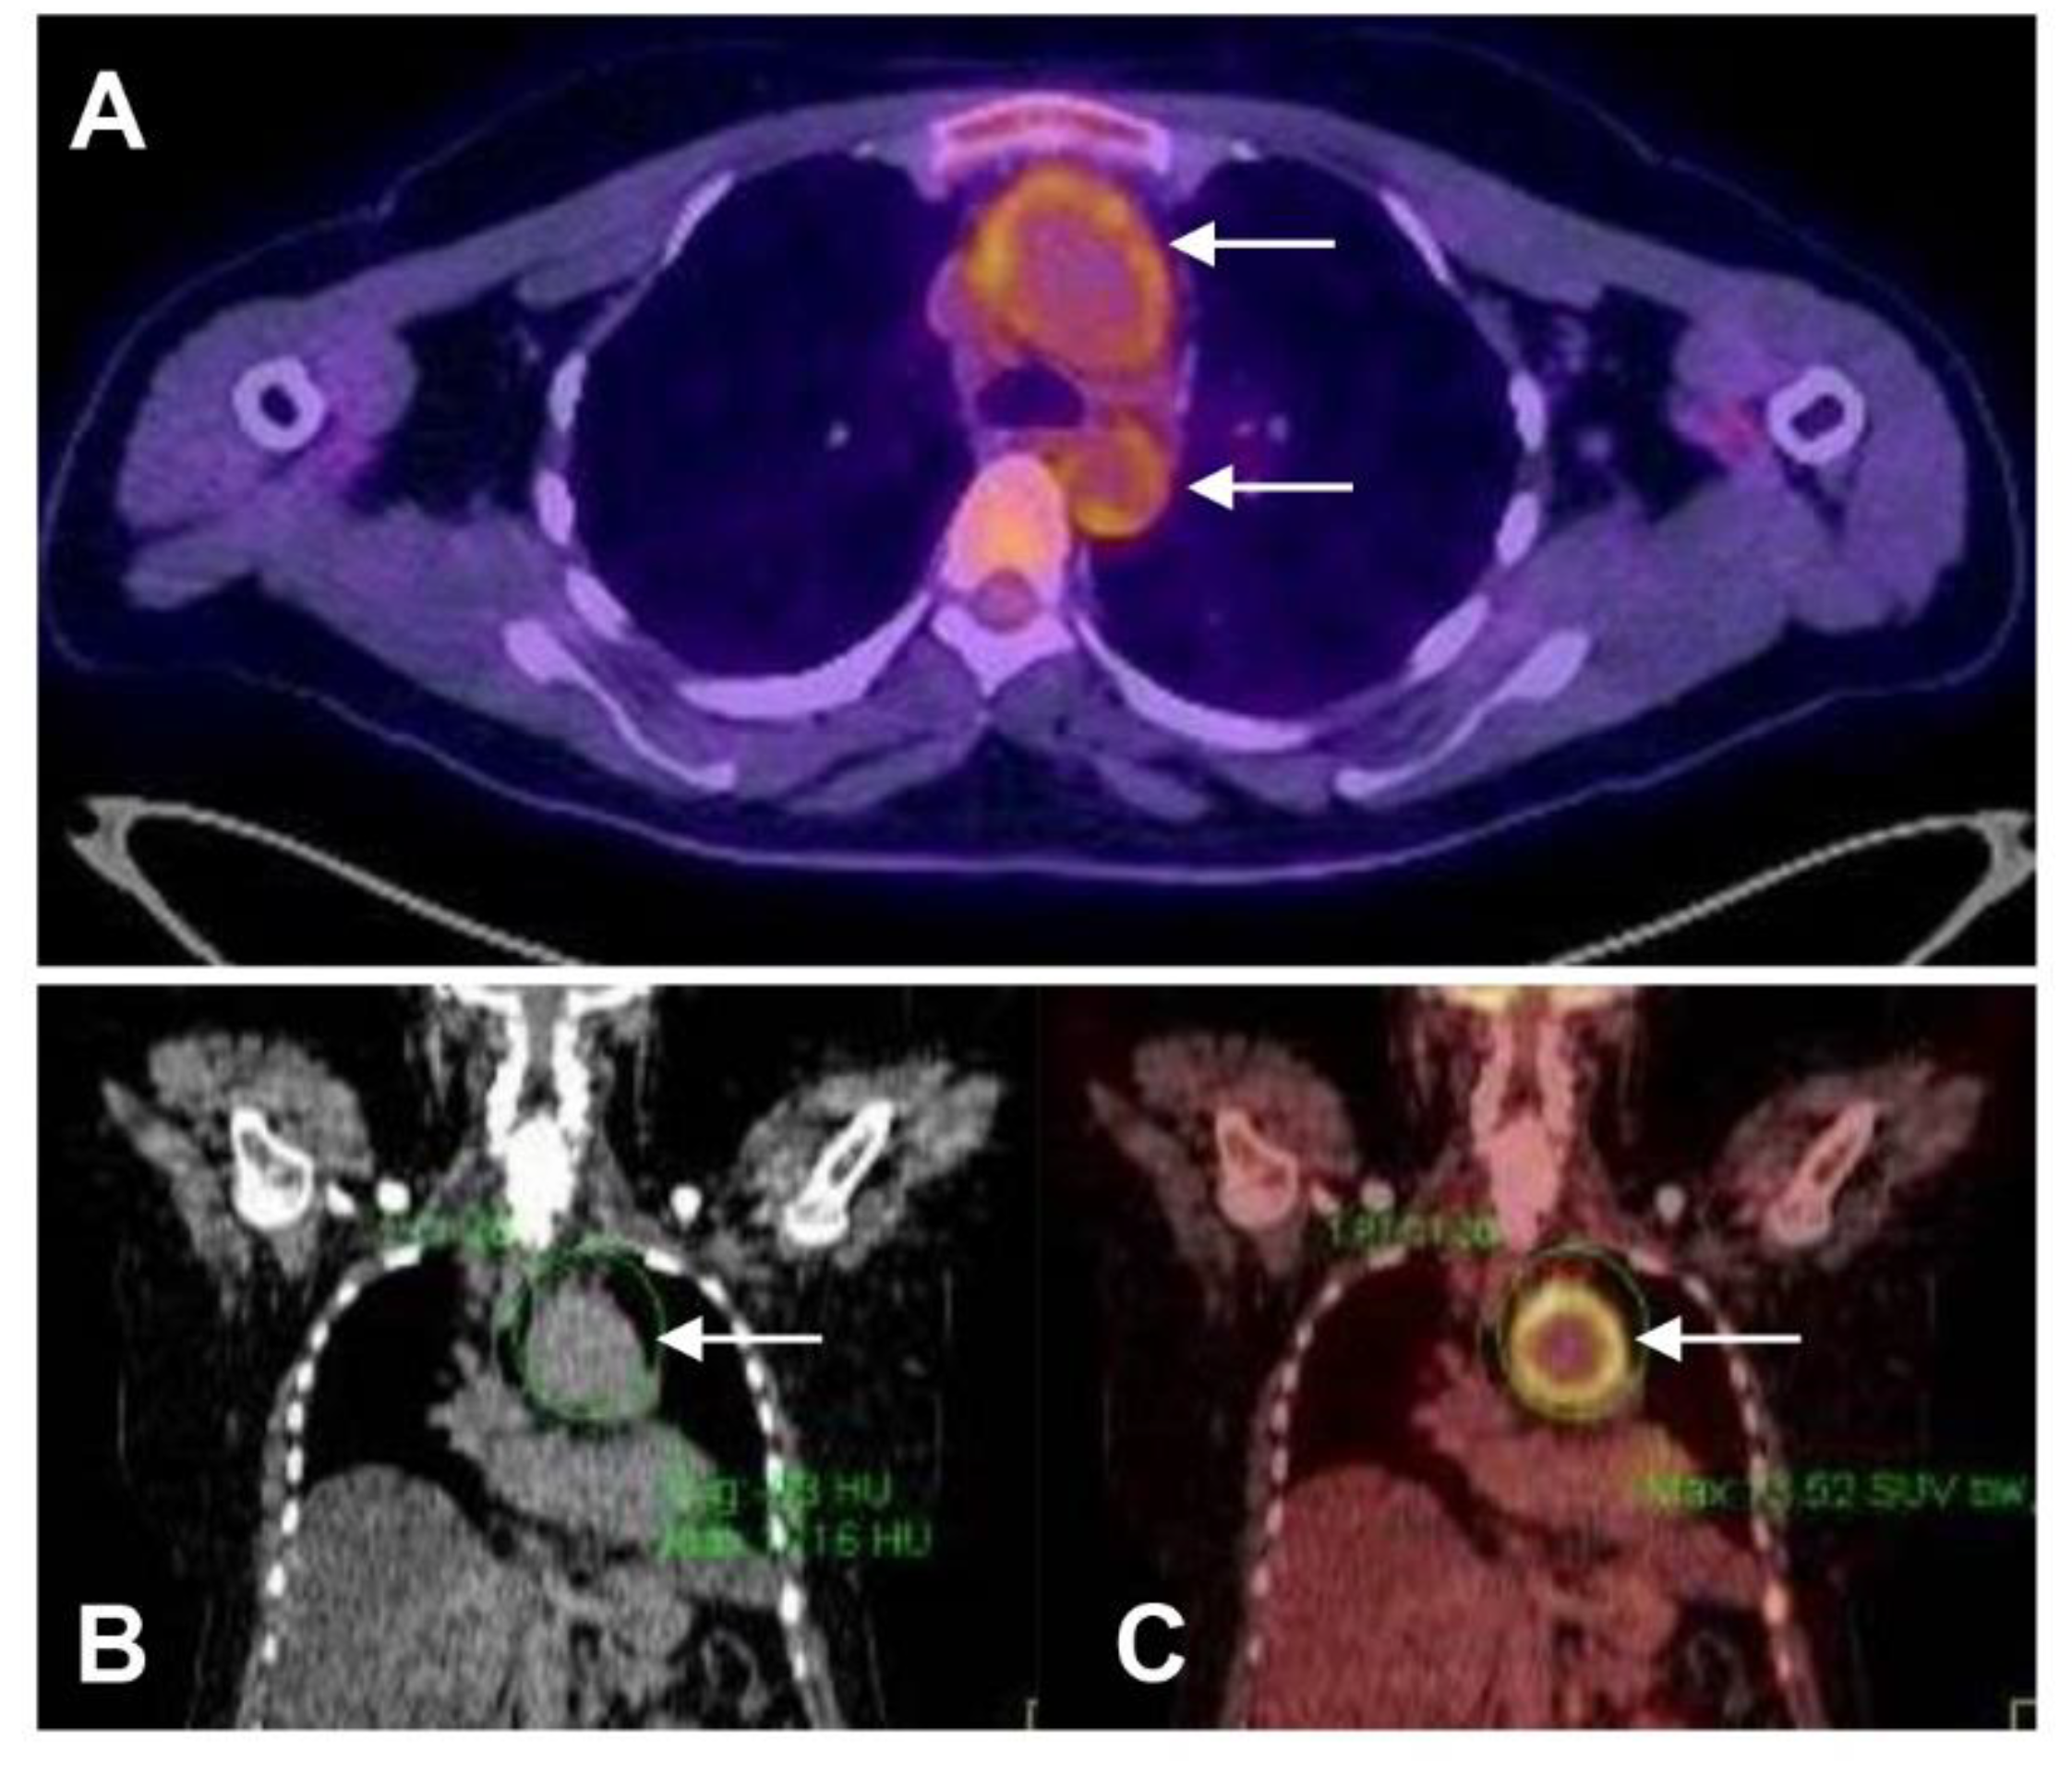

6. Pre-Operative Assessment of Disease Activity

- Grayson, P.C.; Alehashemi, S.; Bagheri, A.A.; Civelek, A.C.; Cupps, T.R.; Kaplan, M.J.; Malayeri, A.A.; Merkel, P.A.; Novakovich, E.; Bluemke, D.A.; et al. (18) F-Fluorodeoxyglucose-Positron Emission Tomography As an Imaging Biomarker in a Prospective, Longitudinal Cohort of Patients With Large Vessel Vasculitis. Arthritis Rheumatol. 2018, 70, 439–449. [Google Scholar] [CrossRef] [PubMed]